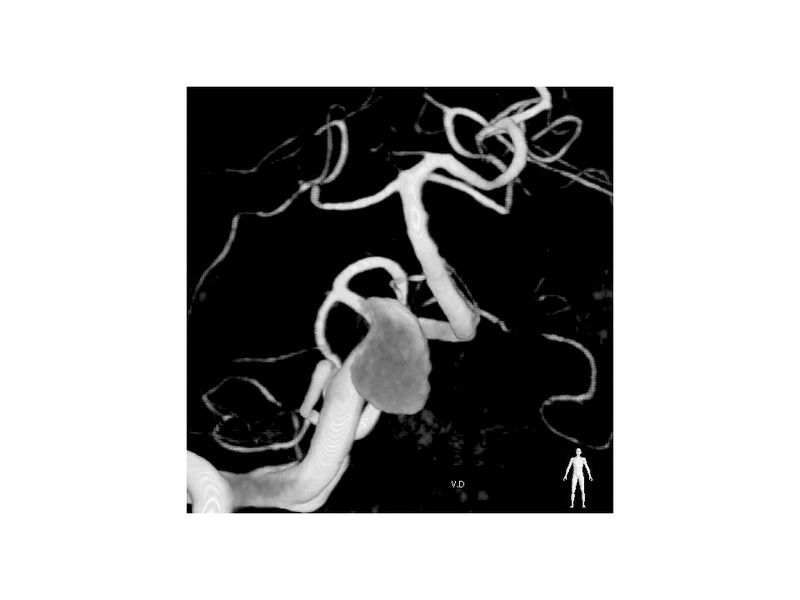

Aneurismas grandes